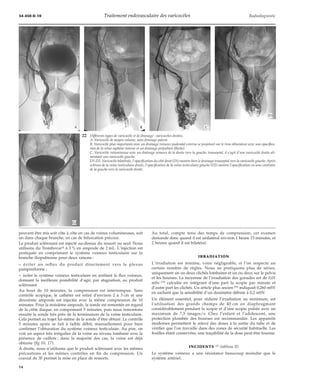

1 Les différentes techniques de traite-ment.

1. Voie rétropéritonéale ; 2. voie coeliosco-pique

; 3. embolisation radiologique ;

4. voie inguinale classique ou microchirur-gie

; 5. voie subinguinale classique ou mi-crochirurgie

; 6. libération testiculaire ; 7.

voie scrotale ; 8. sclérothérapie antegrade.

Thérapeutiques

Huit techniques sont possibles : sept chirurgicales et le traitement

radiologique endovasculaire (fig 1) (tableaux I, II).